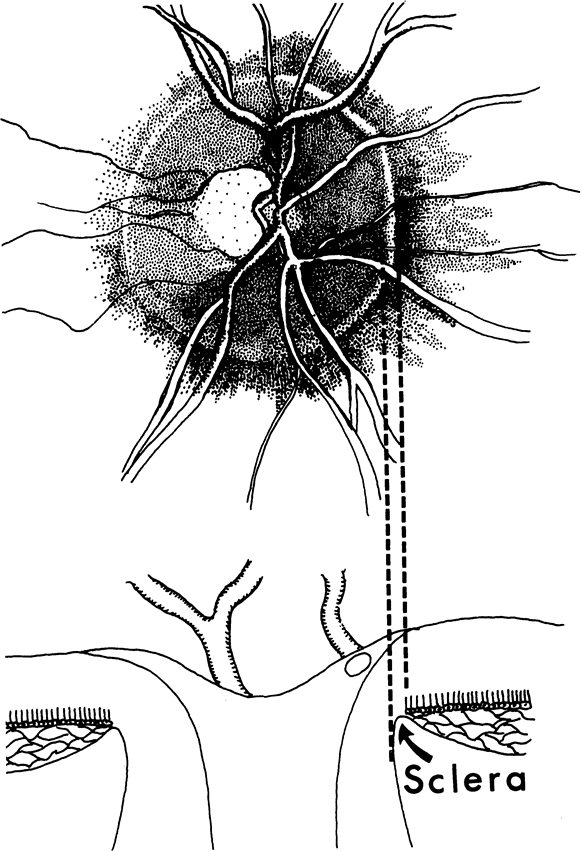

In the retinal nerve fiber layer, axons converge from every direction toward the optic disc and turn to enter the optic nerve through an opening in the outer retina, the choroid, and the sclera. The features and anatomic variation of the normal optic nerve head, or optic disc, are illustrated in Figures 2, 3, 4, 5, 6, 7, 8, 9, 10, 11, 12, 13, 14, 15, and 16. A physiologic excavation (cup) results if the chorioscleral canal is larger than required for the approximately 1 to 1.5 million axons and the supporting glial cells and blood vessels. The size of the excavation depends on how ample is the size of the chorioscleral canal.20,21 In discs where the chorioscleral canal matches the number of axons, the chorioscleral canal itself is typically somewhat taller than it is wide (Figs. 2 and 3). However, because the number of nerve fibers entering the upper and lower poles of the disc is greater than in the temporal and nasal sectors, the boundary of the physiologic cup is more or less circular.22 When the disc is large, it may be nearly circular but the cup likewise nearly circular. However, except in discs of anomalous shape, the width of the rim of neuroretinal tissue is noted in normal, nonglaucomatous optic discs to be greatest in the inferior meridian followed by the superior meridian, and narrowest in the temporal quadrant.23

The canal through which the optic nerve exits from the eye traverses several layers of peripapillary tissue: the outer retina, the pigment epithelium, Bruch's membrane, the choriocapillaris, the outer choroid, and the sclera. In nearly all human eyes, in all or some meridians, a flange of sclera extends as far forward as the pigment epithelium, forming something of a border for the canal,25,26 and this can be seen ophthalmoscopically as a scleral rim around the disc (Figs. 5, 6, and 7). With or without such an obvious flange, the several chorioretinal layers may not be perfectly aligned with one another. Perhaps most typically, as the optic nerve exits obliquely in an upper nasal direction, the lower temporal sector of the disc viewed ophthalmoscopically is seen to have a crescent of misaligned edges of the several chorioretinal layers, such that the outer choroid and sclera may be left uncovered by the choriocapillaris and pigment epithelium (Fig. 8). Because of the tilt, the scleral flange is not seen as a narrow band; instead, by ophthalmoscopy its inner surface is viewed obliquely as it merges with the optic nerve sheath. In some myopic eyes, the crescent is most extensive on the temporal side, and in other eyes the crescent may be directly inferior, or for that matter less frequently in almost any position. In yet other variations the crescent encompasses much or all of the entire circumference of the disc, with misalignment or retraction of the various chorioretinal layers. When these eyes have glaucoma and the thin or retracted choroid surrounds the disc entirely, the area of thin choroid and absent retinal pigment epithelium has been termed a glaucomatous halo. The deformed anatomy associated with the tilted exit canal or the peripapillary crescent may mark the sector of the disc that is most susceptible to injury from elevated intraocular pressure27; for example, the lower temporal sector of the disc is most frequently the first sector affected.